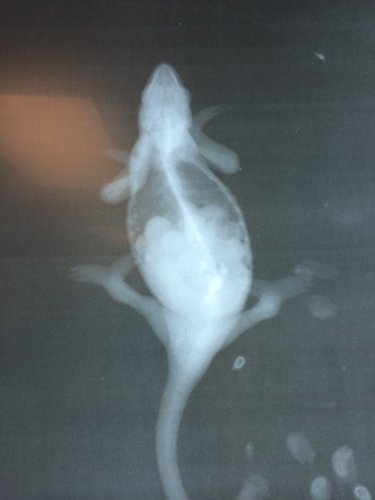

UPDATE - She stayed with the Vet yesterday afternoon, he fed her some high protein dog food, baby food eggs, with Vitamin A and D supplement mixed in. He also gave her an injection of Calcium. Attached is her x-ray, you can see the eggs and also see that her bones look good. Right before I brought her home, he gave her an Oxytocin injection.

• x-ray.jpg

x-ray.jpg

I honestly can't tell too much from the xray shown, but I'm guessing by the looks of those eggs that they are infertile. She honestly looks egg bound to me and when at this stage, oxytocin isn't always effective.

Just peeking in between my appointments so will make this brief. She definitely has MBD (her bone density on the x-ray is horrible in addition to having the classic curved limbs and not being able to support her own weight) and she definitely looks egg bound. Her eggs are not shelled yet from the looks of her x-ray and appear to be in the follicular phase still. I think that's what you may have been referring to jpowell rather than truly infertile. With follicles it means they're either too early to be laid, or they're stuck that way and will never actually get shelled enough to be laid. Oxytocin will not be effective at this stage. And she's in no condition to lay right now given her MBD. If she is strong and trying to be somewhat normal you can give it a few weeks of treating her MBD and if at that point her x-ray has not changed (still tight cluster of very round shapes) then she's in follicular stasis and will need surgical removal. If they look a little more spread out and oval rather than round then they might be progressing to shelled eggs that can be laid. But surgery is often needed with these girls because their bodies are too overwhelmed by the MBD to be able to keep everything else normal.